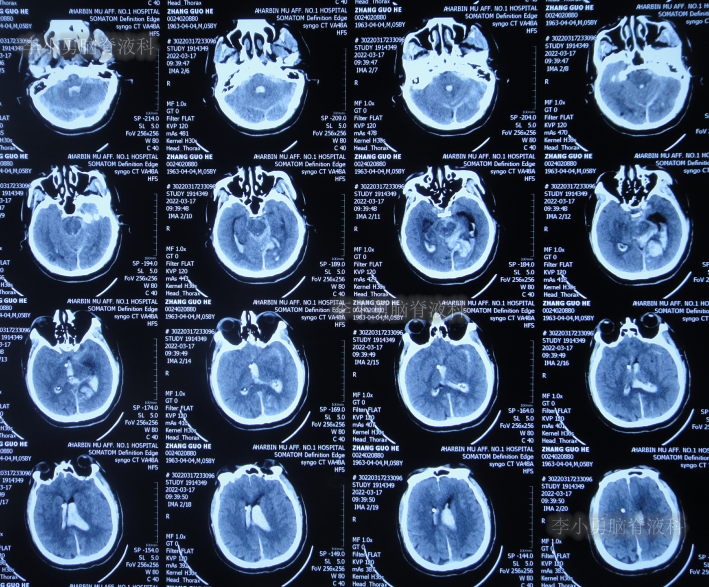

患者于2022年3月16日早晨起床后,无诱因突发头痛,恶心及呕吐,嗜睡,急就诊于当地黑龙江省海伦市某医院,查头颅CT扫描脑出血(片子丢失),因技术有限,120急救车转至上级的黑龙江省哈尔滨某三甲医院,再次复查头颅CT示出血量无明显增多(片子丢失),当天给予脑室外引流术,脑室外引流术后次日查头颅CT示脑出血脑室引流术后(图-1),医生考虑为动脉瘤出血。

图-1:2022年3月17日头颅CT